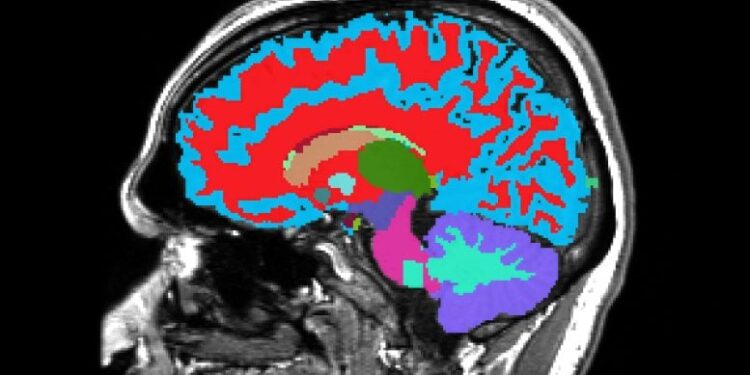

Researchers have created a brand new software that reads how briskly you’re ageing, utilizing only one mind scan. The scan can spot indicators of future illnesses like dementia earlier than signs seem. Folks ageing quicker had weaker reminiscence, extra well being issues, and even a better danger of early loss of life. The software works throughout totally different nations and backgrounds, […]